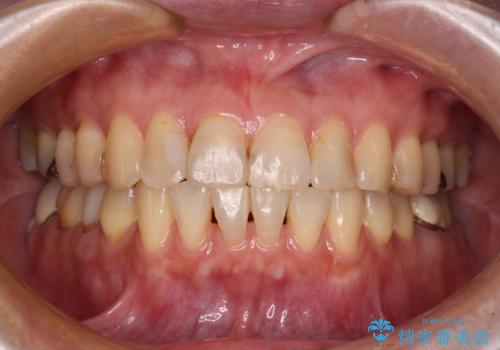

前歯の突出感と上下の隙間 インビザラインによる矯正治療

- 前歯の上下スペースと前歯の隙間を気にして来院された患者様です。

インビザラインにより上下の前歯の隙間を閉じながら、IPRを用いて口元の突出感を合わせて改善していくこととしました。

上下の隙間に舌が入り込むことが、すきっ歯やオープンバイトの原因であったため、舌の筋肉のトレーニングも並行して行い、後戻りの抑制を図りました。